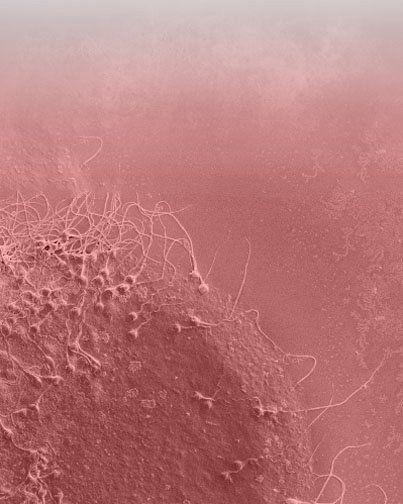

ESTUDIO DE FERTILIDAD PERSONALIZADO

PARA INDIVIDUALIZAR EL TRATAMIENTO